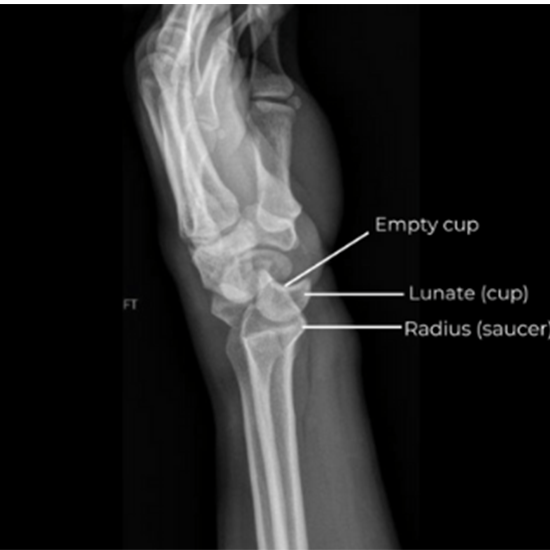

The wrist X-ray shows soft tissues, forearm bones, and eight wrist bones.

A wrist X-ray can show discomfort, edema, or joint abnormalities. Broken bones and dislocated joints can be seen. An X-ray can show if a damaged bone is aligned and has healed appropriately.